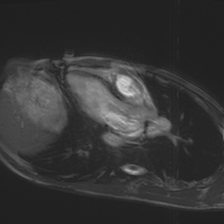

Accurate segmentation and motion estimation of myocardium have always been important in clinic field, which essentially contribute to the downstream diagnosis. However, existing methods cannot always guarantee the shape integrity for myocardium segmentation. In addition, motion estimation requires point correspondence on the myocardium region across different frames. In this paper, we propose a novel end-to-end deep statistic shape model to focus on myocardium segmentation with both shape integrity and boundary correspondence preserving. Specifically, myocardium shapes are represented by a fixed number of points, whose variations are extracted by Principal Component Analysis (PCA). Deep neural network is used to predict the transformation parameters (both affine and deformation), which are then used to warp the mean point cloud to the image domain. Furthermore, a differentiable rendering layer is introduced to incorporate mask supervision into the framework to learn more accurate point clouds. In this way, the proposed method is able to consistently produce anatomically reasonable segmentation mask without post processing. Additionally, the predicted point cloud guarantees boundary correspondence for sequential images, which contributes to the downstream tasks, such as the motion estimation of myocardium. We conduct several experiments to demonstrate the effectiveness of the proposed method on several benchmark datasets.